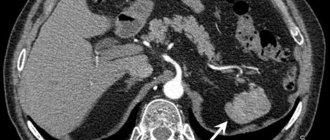

Главная > Симптомы > Боль в левом боку под ребрами Большинство людей связывают боли